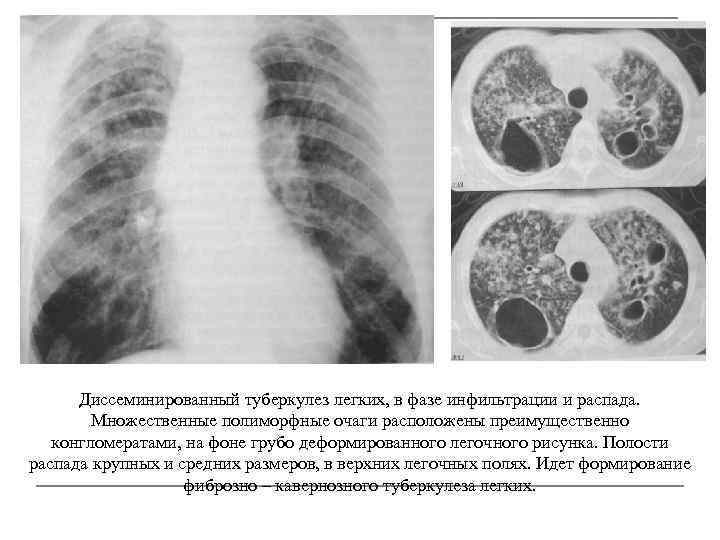

Симптомы и лечение инфильтративного туберкулеза легких

Раздел: Снимки-откровения